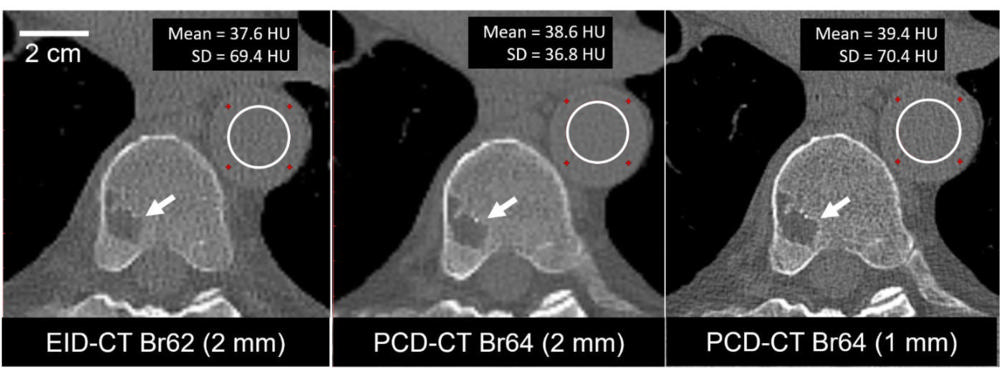

Figure 5. A 74-year-old male clinically indicated for a whole-body low-dose CT skeletal survey for multiple myeloma. Energy-integrating-detector CT (EID-CT) scan (axial image, left) and high-resolution photon-counting-detector CT (PCD-CT) scan (axial image, center and right) were acquired using the same radiation dose (4.2 mGy). PCD-CT images (center) using the same section thickness (2 mm) as EID-CT images (left) showed 47% lower noise (69.4 HU vs. 36.8 HU). Use of thinner (1 mm) section thickness (right) and 1024×1024 matrix resulted in image noise comparable to EID-CT and improved the delineation of a vertebral lesion (arrow). Display window/level = 1500/150 HU. SD: standard deviation of pixel values in the region-of-interest.